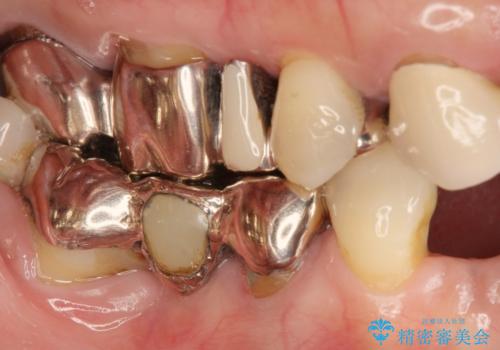

[ 上顎多数歯欠損 ] インプラント・義歯を用いた補綴

![[ 上顎多数歯欠損 ] インプラント・義歯を用いた補綴の症例 治療前](https://seimitsushinbi.jp/wp/wp-content/uploads/2020/09/df191d89bffff661c1e5377feed6ed49-500x350.jpg?v=1600566138)